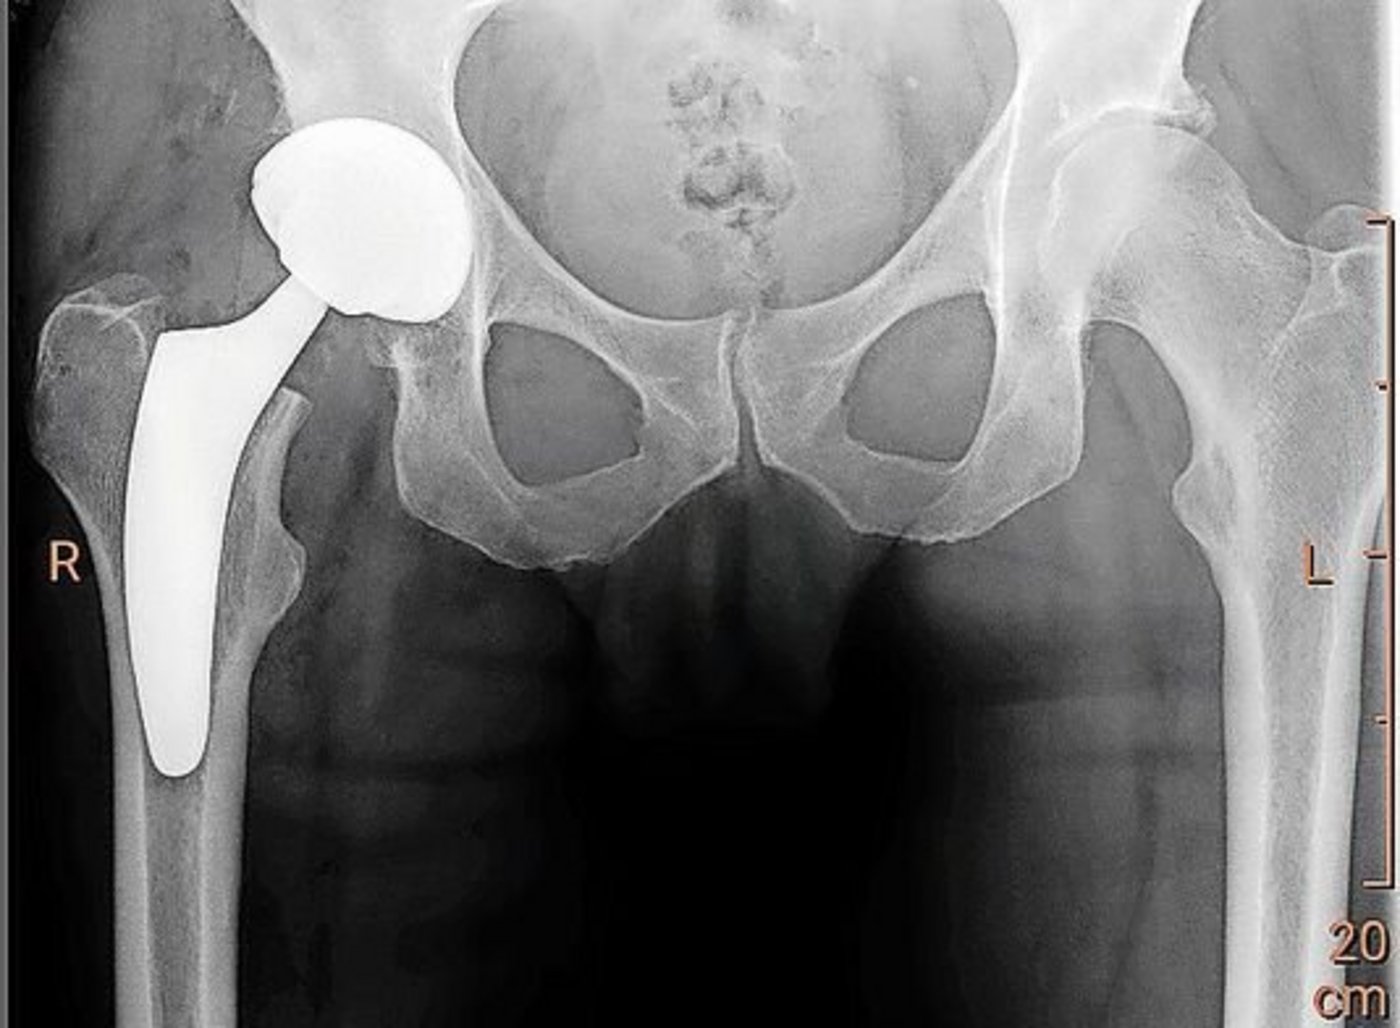

Die Prothese, also ein künstliches Gelenk, sollte immer die letzte Variante einer Behandlungsoption sein. Vorher sollten Therapiemöglichkeiten wie aktive und regenerative Bewegung mit Schwimmen und Velofahren oder andere mit der Physiotherapie erarbeitete Massnahmen in Betracht gezogen werden. Sind anhand eines MRIs bereits grössere Schäden im Gelenk erkennbar, können zum Teil mit einer Kniespiegelung degenerative Komponenten wie beispielsweise kleine lose Knorpelpartikel entfernt oder auch Meniskusrisse behandelt werden. Dadurch wird die Reizung der Gelenke meist deutlich reduziert. Wird diese Massnahme mit aktiver Bewegung kombiniert, kann eine Prothese teils noch länger hinausgezögert werden. Etwas Zeit gewinnen kann man auch durch Spritzen mit Kortison, Hyaluron oder Eigenblut, die direkt in das schmerzende Gelenk verabreicht werden.

Komplikationen sind heute zum Glück selten. Die Qualität der Gelenkchirurgie und auch die der Gelenkimplantate ist mittlerweile sehr hoch. Die Kunststoffmaterialien der Implantate nutzen sich kaum noch ab. Was eher vorkommt, sind Lockerungen der Implantate infolge von Stürzen, fortgeschrittener Osteoporose oder Infekten.

Wichtig ist, dass sich Menschen mit Prothesen allgemein vor bakteriellen Infekten in Acht nehmen, denn diese können über die Blutbahnen in den Bereich der künstlichen Gelenke gelangen und dann dort zu Entzündungen und Infektionen führen. Für den Einbau einer Gelenkprothese kann man aus medizinischer Sicht kaum zu lange zuwarten. Man sollte spätestens dann zum Arzt gehen, wenn die Beschwerden so gross werden, dass man den Alltag nicht mehr problemlos meistern kann.

[IMG 2]